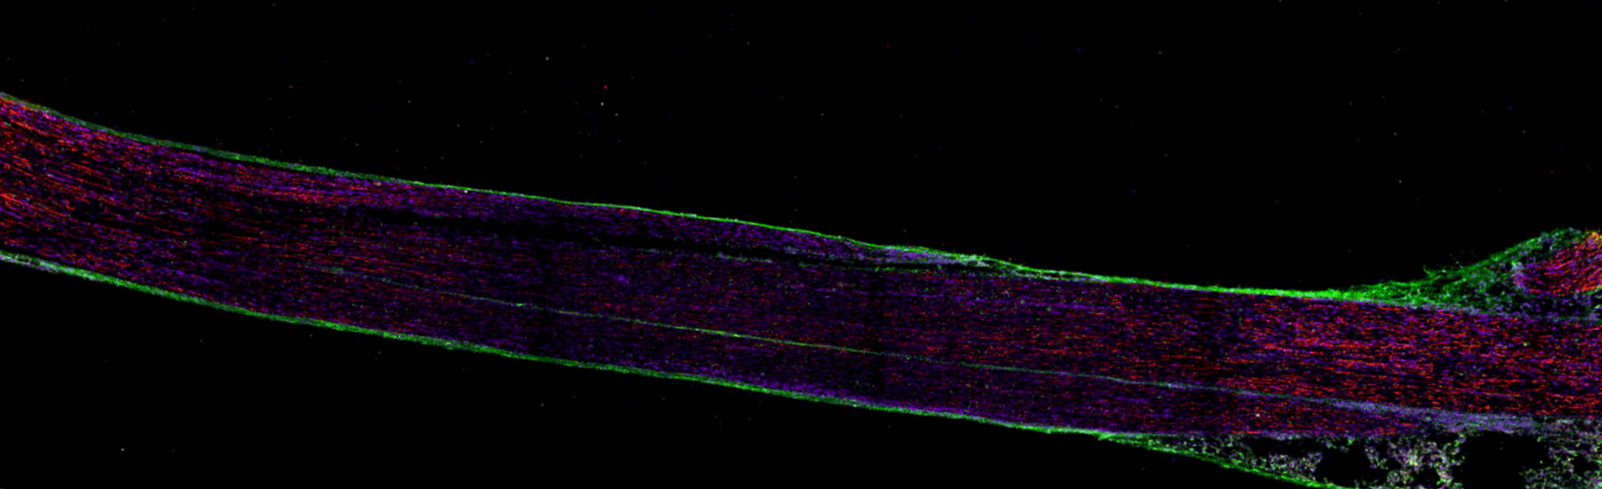

Chronic pain after nerve injury is traditionally attributed to malfunctioning sensory neurons. However, evidence suggests that non-neuronal cells in the peripheral nerves, particularly immune cells, play a critical role regulating pain. We are mapping the immune atlas of human and mouse nerves in healthy and painful states to decipher immune mechanisms that contribute to the development and maintenance of neuropathic pain. Our goal is to “reset” the immune system to achieve long-term analgesia.

Related publications: Macrophages protect against sensory axon degeneration in diabetic neuropathy.